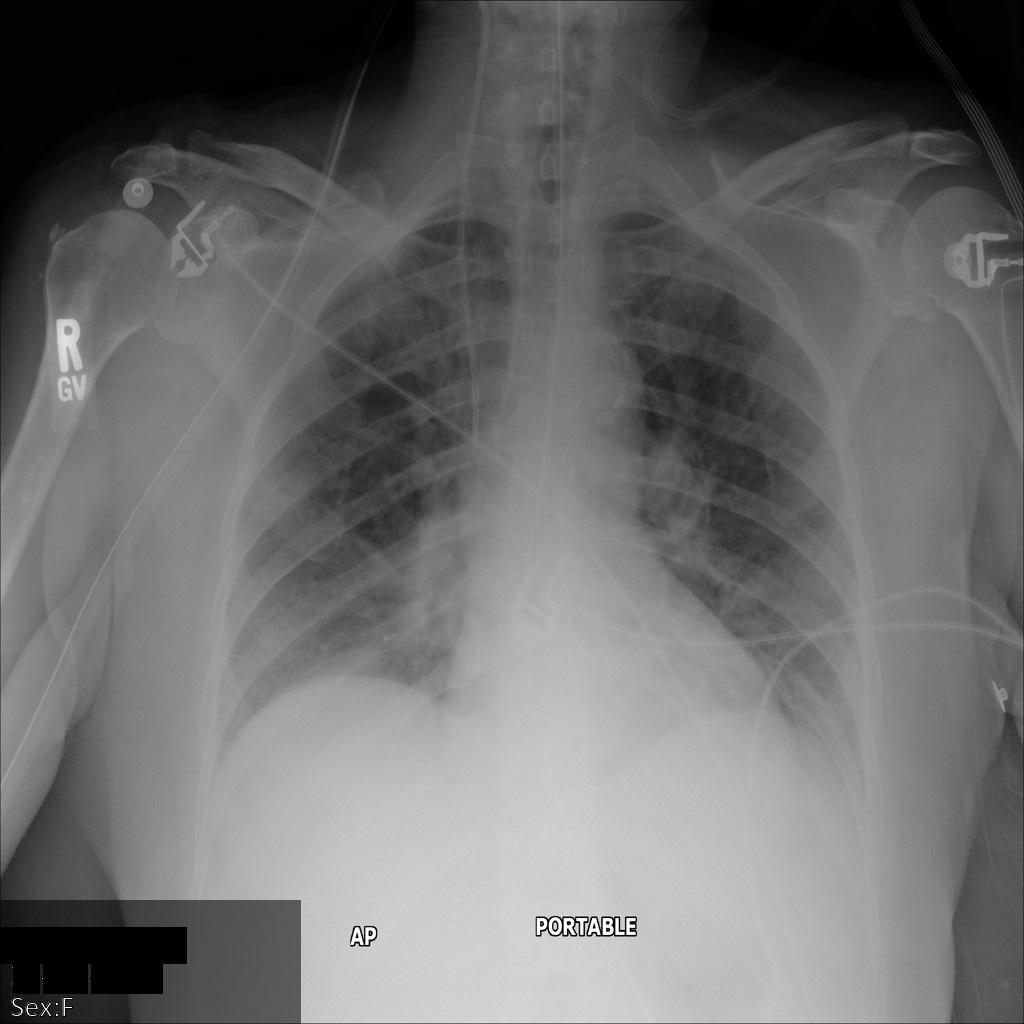

L'image suivante montre une radiographie non masquée d'un patient :

Une fois l'image envoyée à l'API Cloud Healthcare à l'aide de l'option REDACT_SENSITIVE_TEXT, elle apparaît comme suit :

Vous pouvez constater que les événements suivants se sont produits :

- Le paramètre

PERSON_NAMEen bas à gauche de l'image a été masqué. - Le paramètre

DATEen bas à gauche de l'image a été masqué.

Le sexe du patient n'a pas été masqué, car il n'est pas considéré comme du texte sensible selon le paramètre infoTypes DICOM par défaut.